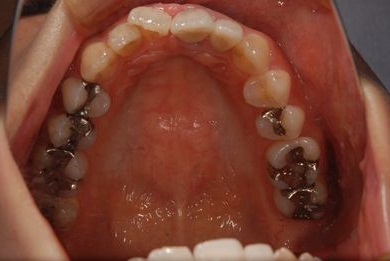

| 性別/年齢 | 女性 / 31歳 | ||||||||||||||||||||||||||||||||

| 主訴 | 前歯の歯茎が黒ずんでいるので、改善したい。 | ||||||||||||||||||||||||||||||||

| 治療方針 | 上顎前歯、メタルボンドセラミッククラウンからオールセラミッククラウンにする事で、審美的回復を行う。 | ||||||||||||||||||||||||||||||||

| 治療内容 | CAD/CAMオールセラミッククラウン2本(セラミック用土台2本) | ||||||||||||||||||||||||||||||||

| 総治療費 | 142,800円 | ||||||||||||||||||||||||||||||||

| 治療期間 | 2ヶ月 |